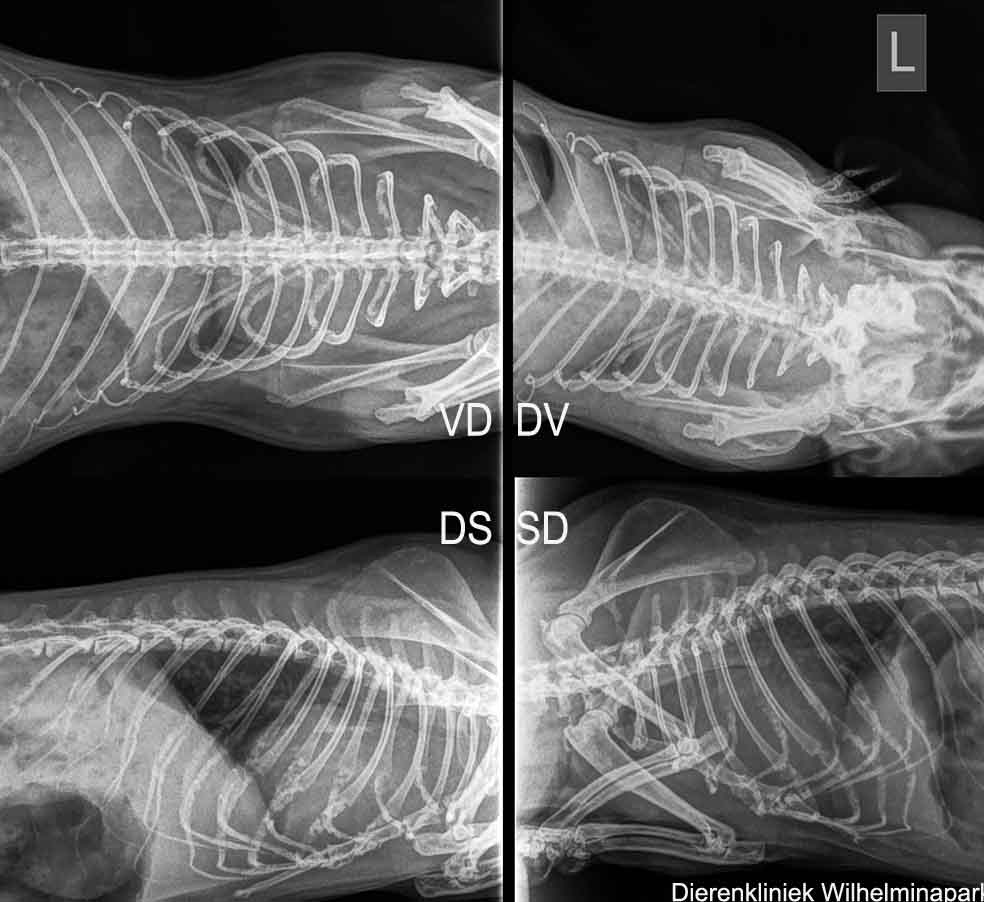

Bij cavia Roos was er ook een hartprobleem ....

Het hart bij cavia Roos was niet vergroot bij cavia Roos, maar op de echo was te zien dat er een hartprobleem speelde.

We hebben een echo van het hart laten maken:

We hebben röntgenfoto's gemaakt van de borstholte.

We hebben röntgenfoto's laten beoordelen.

We hebben een echo laten maken van de borstholte. Helaas kwam er een verdenking van een tumor uit dit echografisch onderzoek.